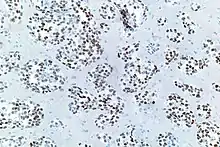

Metachromatic leukodystrophy

Metachromatic leukodystrophy, also known as MLD, is a recessive lysosomal storage disorder. It is believed to be caused by a deficiency in arylsulfatase A.[1][9] Arylsulfatase A is a lysosomal sulfatase that is able to hydrolyze the 3-O-sulfogalactosylceramide and 3-O-sulfolactosylceramide. Both 3-O-sulfolactosylceramide and 3-O-sulfogalactosylceramide can be located mainly in the central nervous system as well as in the peripheral nervous system.[1] When lacking the lysosomal enzyme or mutations in the gene coding for saposin B occur, this can lead to the accumulation of lysosomal sulfatide, which then develops into metachromatic leukodystrophy.[1][3]

Sulfatide plays an important role in the myelin. Myelin acts as an insulating sheath that surrounds many nerve fibers and increases the speed at which impulses are conducted. When sulfatide is not distributed properly, it can affect the normal physiological conduction of electrical impulses between nerve cells.[1] This then results in demyelination because of the buildup of sulfatide and is the main cause of Metachromatic Leukodystrophy.[1][3]

However, how sulfatide buildup causes demyelination and neural degeneration is still mostly unknown.[1] Metachromatic Leukodystrophy results in neurological manifestations that are centered on the impairment of the central nervous system and the peripheral nervous system, including the following: seizures, progressive coordination and speech problems, and behavioral disturbances.[10] Treatment is still being studied and evaluated, but mice studies indicate that treatments, including gene therapy, cell-based therapies using oligodendrocyte progenitors cells, enzyme replacement therapy, or adeno-associated viral and lentiviral mediated gene therapy may prove to be effective in reducing the effects of Metachromatic Leukodystrophy.[1]